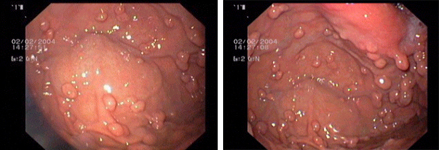

imagen1

Endoscopic image of a flat polyp in the colon, before (left) and after resection.